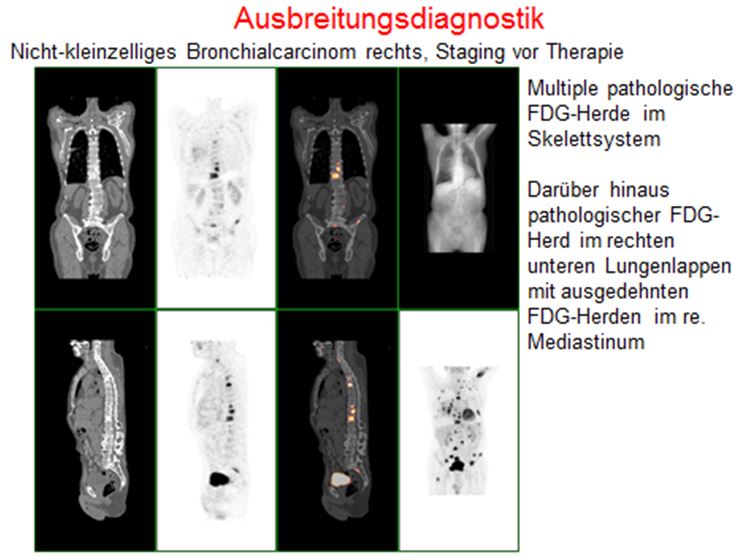

- Bronchialkarzinome

Die PET-CT gilt als eines der genauesten Diagnoseverfahren in der Tumordiagnostik. Mit ihr kann man kleinste Tumorherde und Metastasen in einer einzigen Ganzkörperuntersuchung erfassen und lokalisieren.

Die PET-CT ist zusätzlich ideal zur Kontrolle des Therapieverlaufs bei einer bestehenden Tumorerkrankung, aber auch zur Früherkennung von Tumorerkrankungen geeignet. Bei der Nachsorge kann mit einem Blick geklärt werden, ob Metastasen vorhanden sind oder nicht.